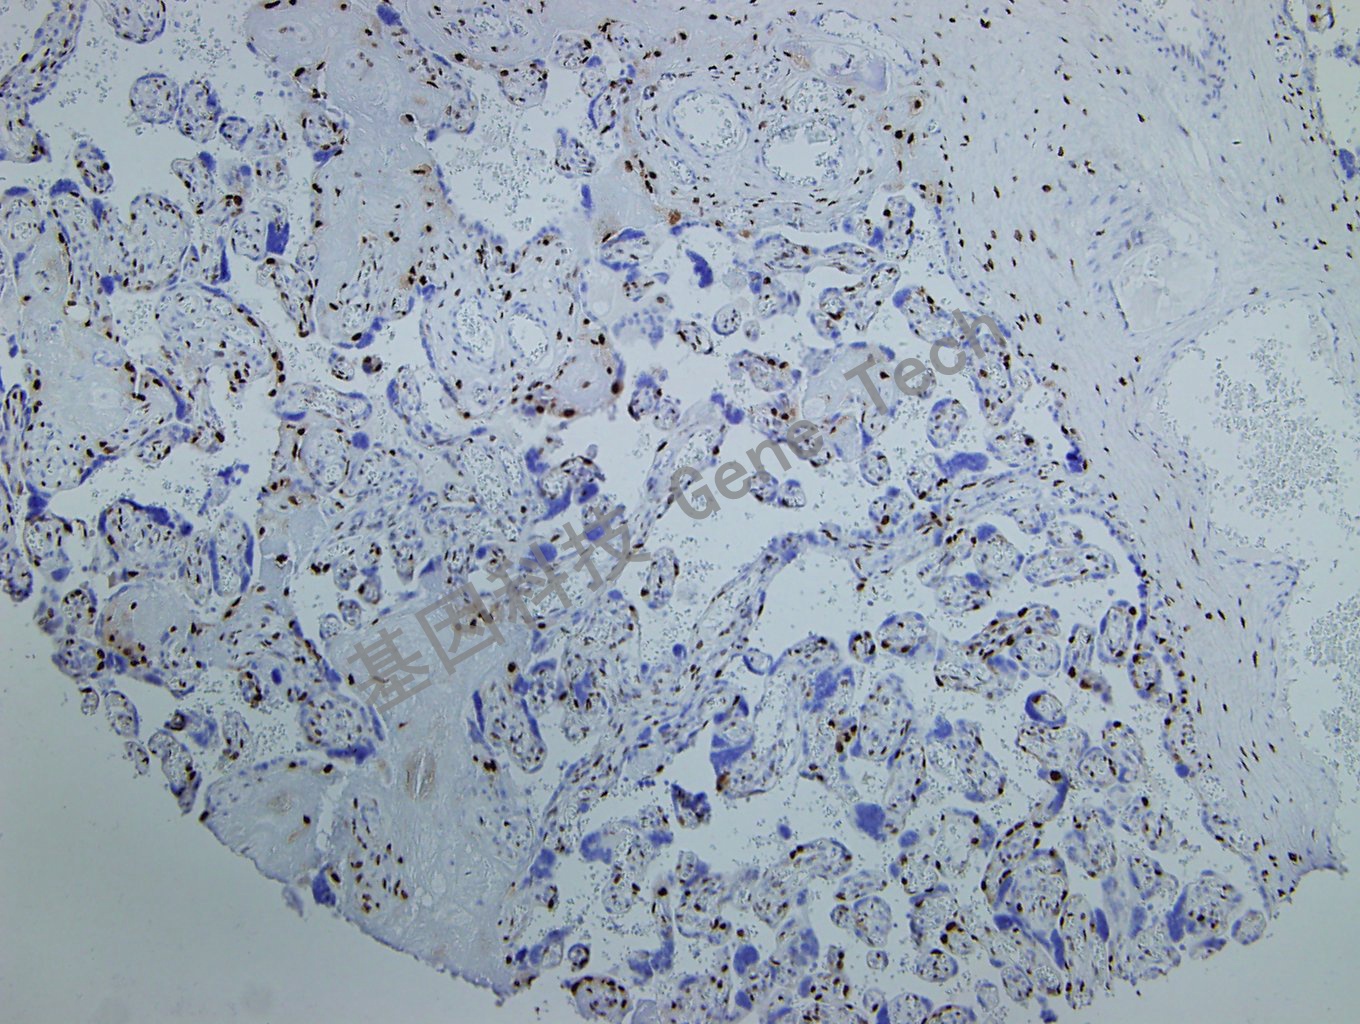

完全性葡萄胎石蜡切片,用 p57(GT2069)染色,细胞核阳性,DAB 显色。